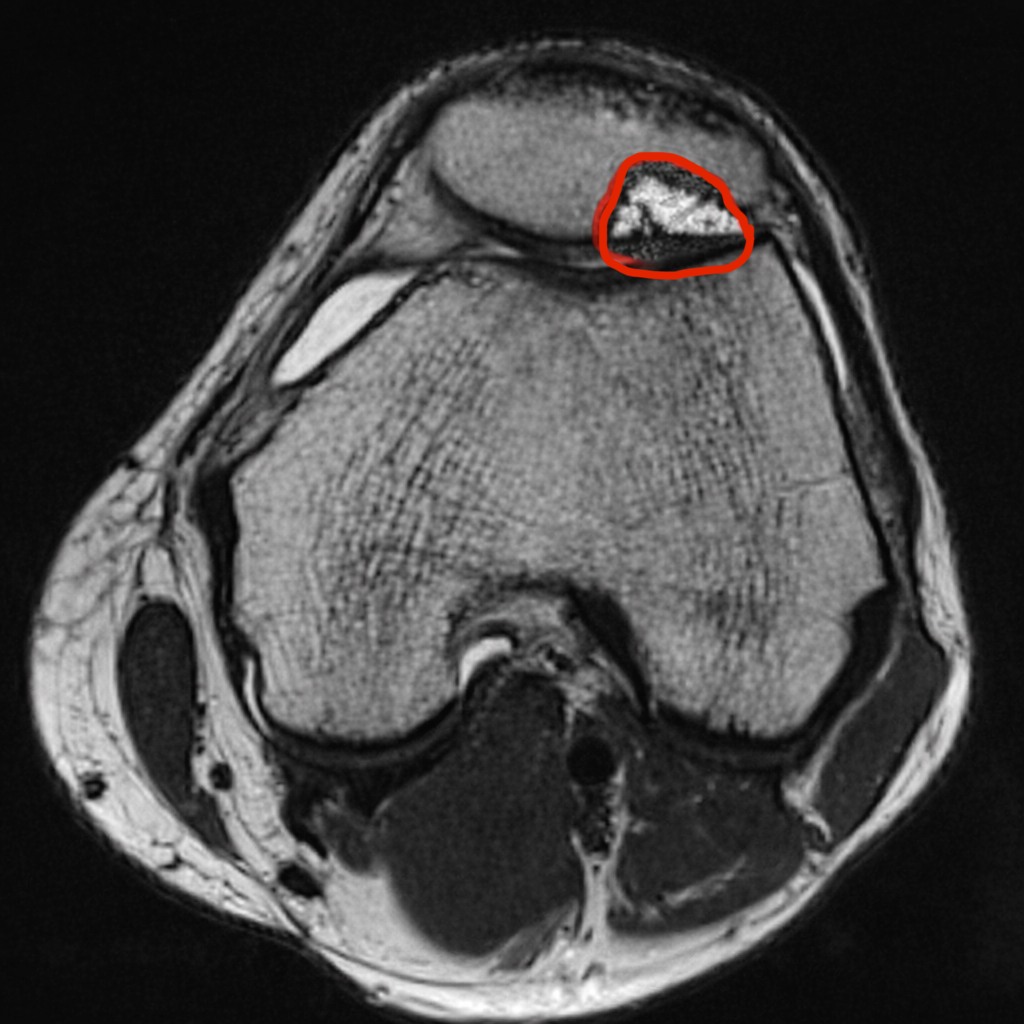

Після МРТ медики встановили діагноз — хондромаляція надколінника IV ступеня (глибоке руйнування хряща).

«Якби пацієнт не звернувся вчасно, процес міг перейти на стегнову кістку, порушилась би біомеханіка коліна, а в крайньому випадку все могло завершитися ендопротезуванням», — пояснив травматолог лікарні Андрій Чужак.

Медики провели малоінвазивну операцію за сучасною методикою AMIC (Autologous Matrix-Induced Chondrogenesis). Втручання виконали закритим способом через малі доступи. Під час операції очистили ушкоджену ділянку хряща, здійснили мікрофрактурування кістки, автотрансплантацію губчастої кістки, застосували PRP-терапію та автологічні стовбурові клітини, після чого дефект закрили багатошаровою колагеновою мембраною.